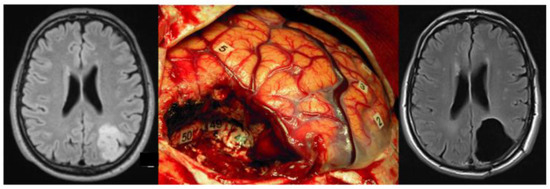

4. PTZ Recognition Supports Supratotal Resection and Vice Versa